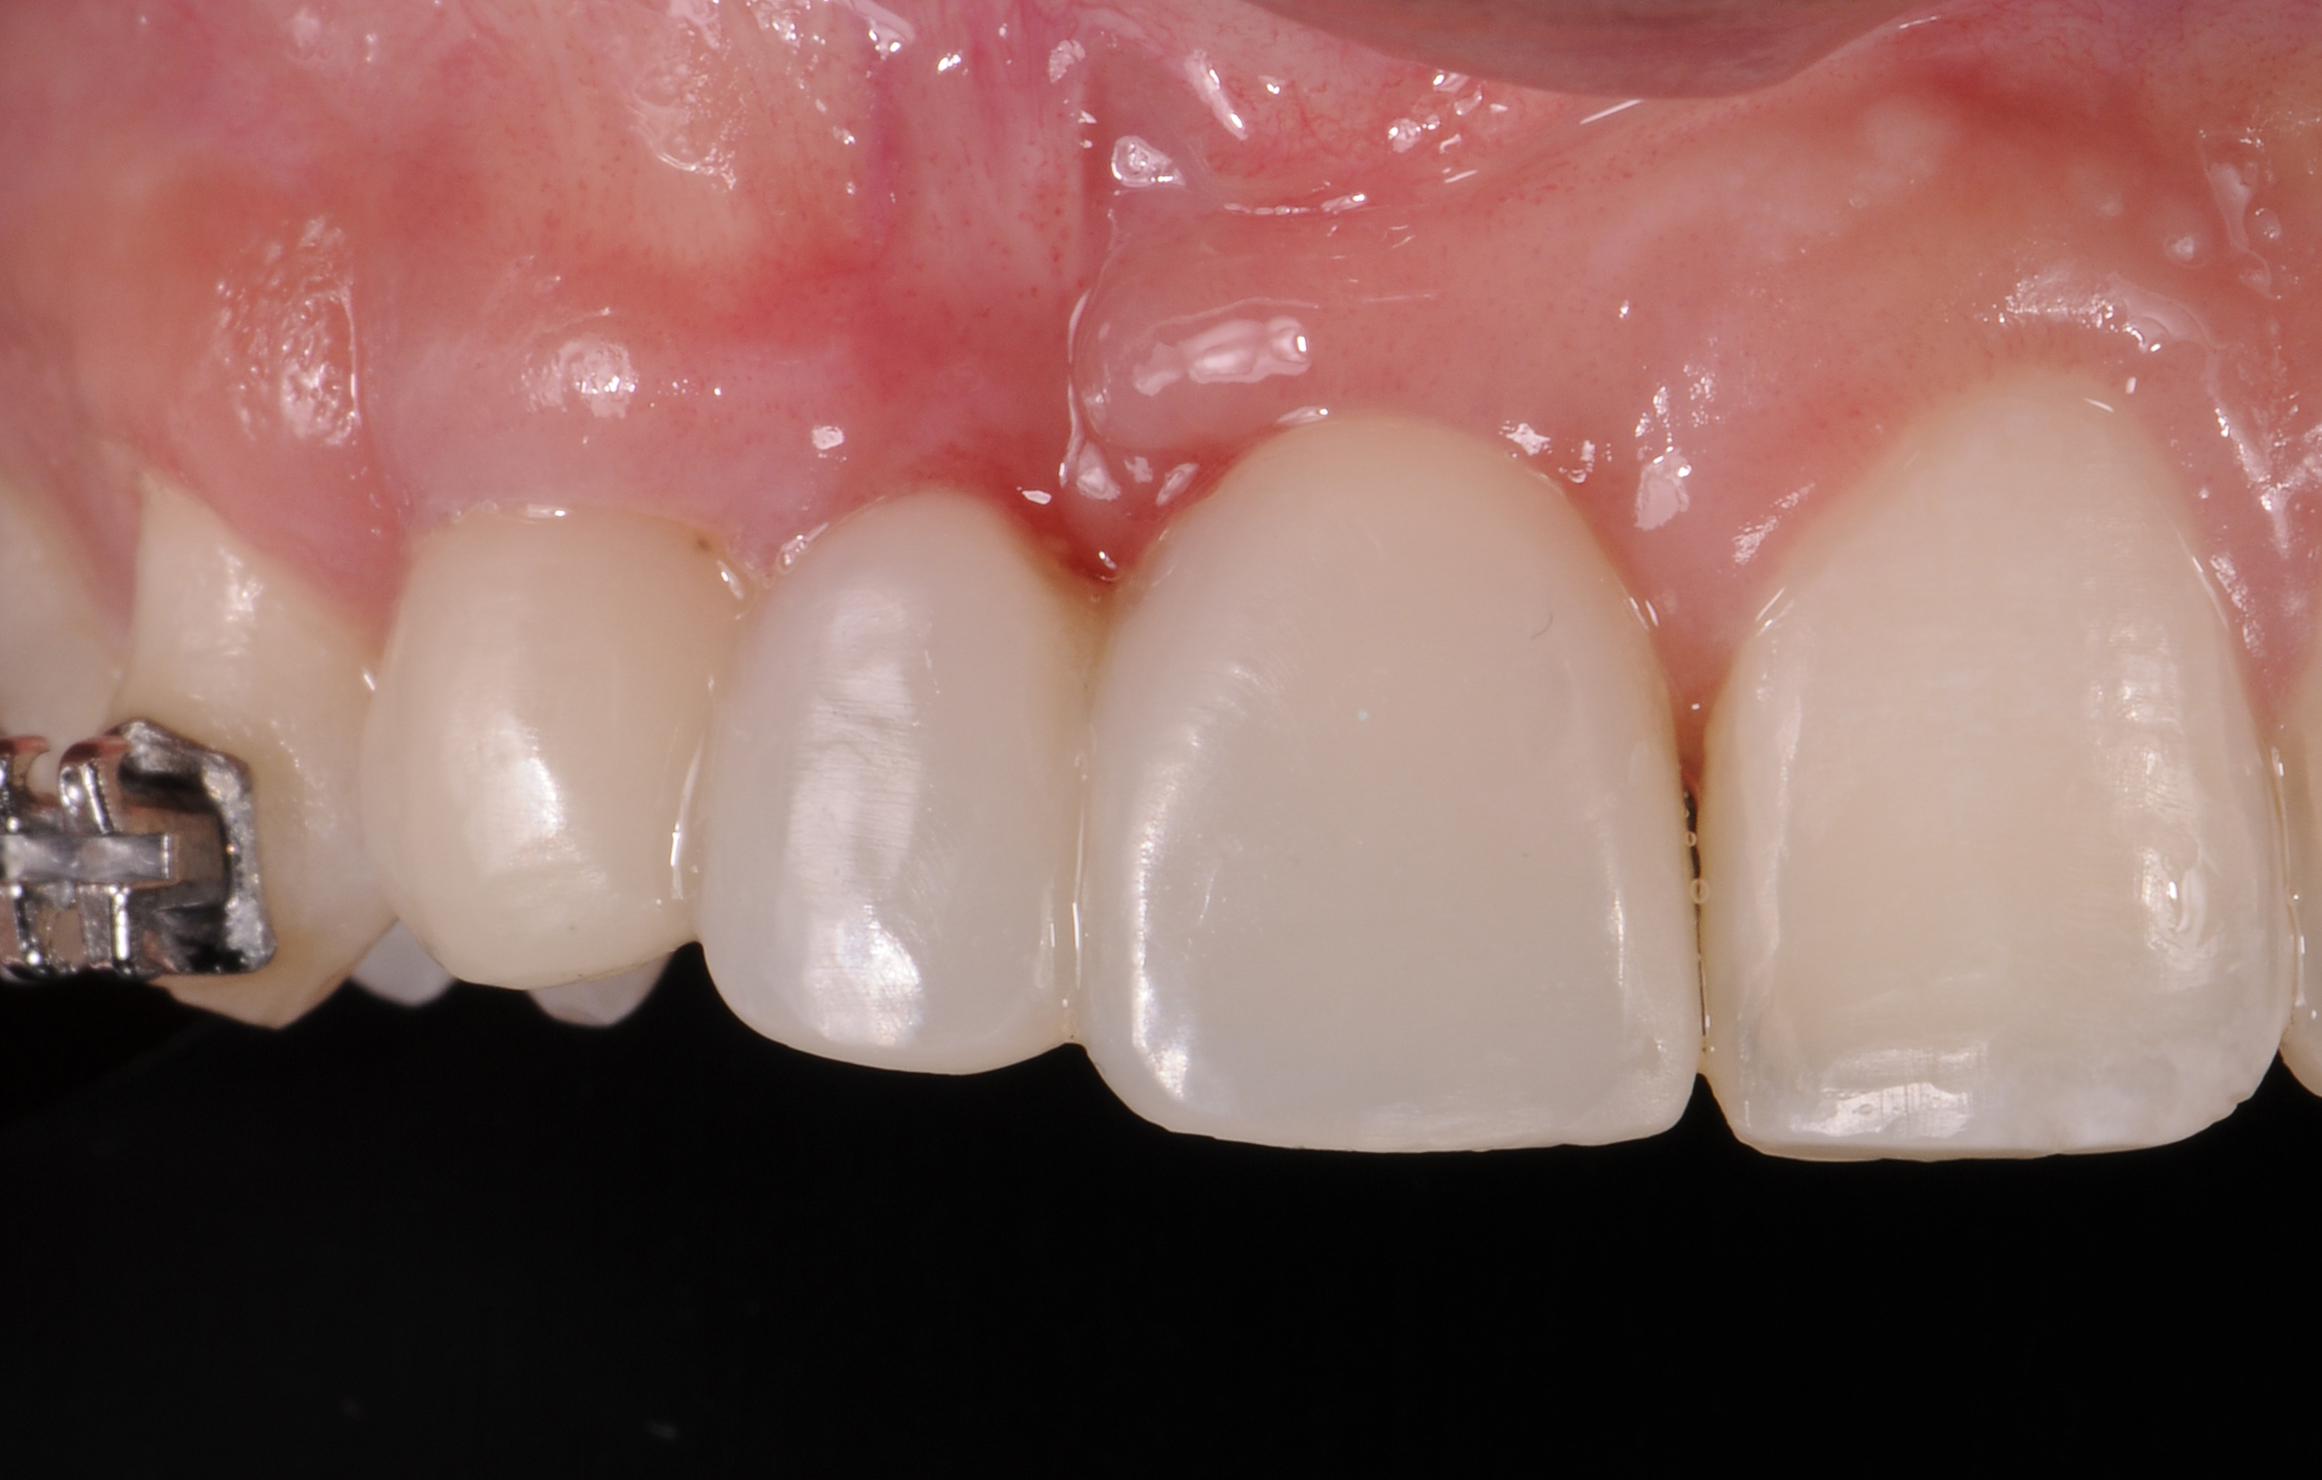

The intraoral examination revealed a substantial deficit of alveolar bone and gingival tissues in the maxillary right lateral incisor area. The ridge defect exhibited vertical and horizontal components, which were associated with a severe loss of clinical attachment on both the mesial aspect of tooth No. 6 and the distal aspect of tooth No. 8. Although probing depths were within normal limits, minimal keratinized gingiva was present and the soft tissues were acutely inflamed. Plaque removal was difficult because of the soft-tissue defect, gingival-margin location, and irregular soft-tissue architecture. Additionally, bone sequestration could be observed through the labial mucosa (Figure 2).

When forced eruption is completed, the teeth should be splinted for a 3-month stabilization period,30 which will allow mineralization of osteoid tissue and settling of the gingival remodeling process. The degree of forced eruption in the present case was such that extreme mobility precluded the use of a provisional restoration. Instead, a metal-reinforced direct composite splint extending from teeth Nos. 6 to 8 was fabricated in situ (Figure 8 and Figure 9). When compared with the preoperative condition (Figure 2), Figure 8 and Figure 9 depict the treatment progression with forced eruption. The restoration of adequate alveolar height was achieved while enhancing the soft-tissue architecture, and the everted sulcular epithelium on tooth No. 8 proceeded to develop keratinization. However, the pre-existing defect still manifested itself in the form of a residual cleft.